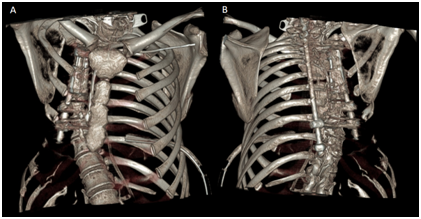

<strong>Figure 6 </strong> 3D tomographic reconstruction showing progression of the disease characterized by absence of right rib cage. A) Anteroposterior view. B) Posteroanterior view.

Figure 6 3D tomographic reconstruction showing progression of the disease characterized by absence of right rib cage. A) Anteroposterior view. B) Posteroanterior view.

<strong>Figure 7 </strong> Presence of osteosynthesis material in the dorsal column for correction of dorsal scoliosis in 3D reconstruction. B) 3D tomographic reconstruction osteosynthesis material used.

Figure 7 Presence of osteosynthesis material in the dorsal column for correction of dorsal scoliosis in 3D reconstruction. B) 3D tomographic reconstruction osteosynthesis material used.

The laboratory studies initially included blood count, serum electrolytes (sodium, potassium, chloride, phosphorus, calcium), coagulation times and liver function tests, where only elevation of leukocytes with predominance of neutrophils was observed, which were associated with the infectious process. The rest of the laboratory tests were within normal ranges. The study of the pleural fluid showed exudate with Gram negative stain, smear microscopy and negative cultures. Therefore, diagnosis of typical parapneumonic effusion was integrated. It was managed with antibiotic therapy and thoracentesis with evolution towards improvement. During hospitalization, progression of bone lysis was observed in the right scapular region and right rib cage, which is why an approach was made to rule out the possible causes of osteolysis.Laboratory studies included: TSH: 1.071mU / L (T3 and T4 were not performed)Glucose 100mg / dLCD3 lymphocyte subpopulations: 472 / 69.2%CD4: 84 / 12.3% CD8: 306 / 44.8% C4 / CD8 ratio: 0.3 C3 complement: 118C4: 29 IgG: 1620 IgM: 125 IgE: 93.9Anticardiolipin IgM 2.3 MPL u / mL IgG GPL u / mL 4.90Antinuclear antibodies: mitochondria anti JO-1, anti-SCL-70, anti-DNAdc, anticelHEP-2 positiveAntinuclear antibodies DNA: ro. anti-ant9 sm / rnp, anti-JO-1, anti SCL-70, anticentromere negative, paratohormone 10 pg / mL The patient was also assessed by the orthopedic service for the congenital scoliosis,  T4-T5 listhesis and T6 compression of medullary canal (Figure 5). It was managed with sublaminar wiring and placement of Luque bars from T2 to T10 and medullary decompression at the T6 level (Figures 6 and 7). The was discharged after the surgical procedure, without supplementary oxygen and in control by external consultation.